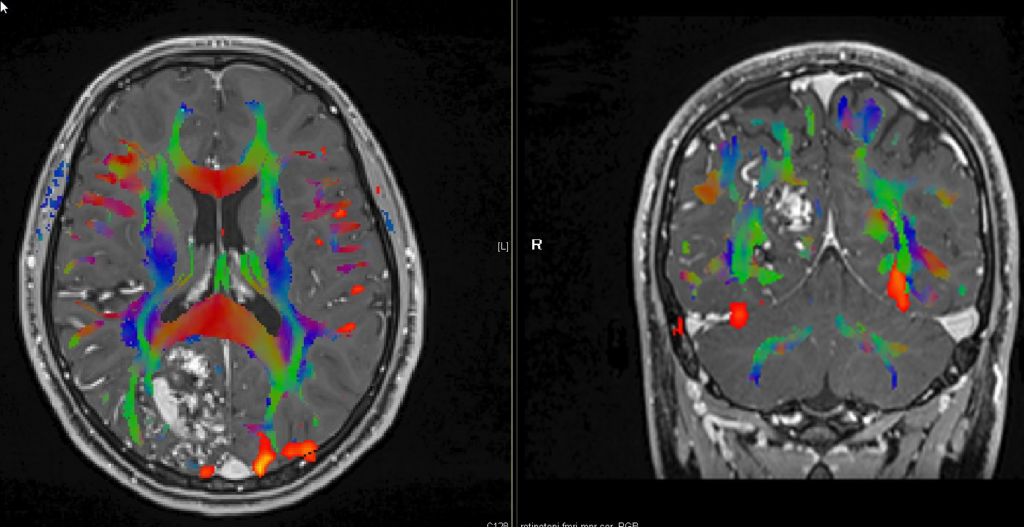

MR Tractography (Magnetic Resonance Tractography) is a specialized imaging technique that uses magnetic resonance imaging (MRI) to visualize the white matter tracts in the brain, which are responsible for transmitting information between different regions of the brain. This technique provides a 3D map of the brain’s neural pathways—such as the corticospinal tract, corpus callosum, and optic radiation—by detecting the orientation and direction of water diffusion along the nerve fibers. This allows clinicians to see and track the fibers that make up these pathways in high detail, providing an understanding of how different regions of the brain communicate with each other.

MR Tractography offers a high-resolution, non-invasive method for visualizing the white matter tracts that are essential for brain function. This allows neurosurgeons to map complex neural networks with high precision, providing them with detailed anatomical information that is critical for planning surgeries around functional brain areas.

MR Tractography significantly enhances preoperative planning, providing a comprehensive map of the brain’s white matter. This 3D mapping helps the surgeon visualize the spatial relationship between tumors, vascular malformations, and important brain tracts, ultimately improving surgical precision and reducing the likelihood of inadvertent damage to critical structures.